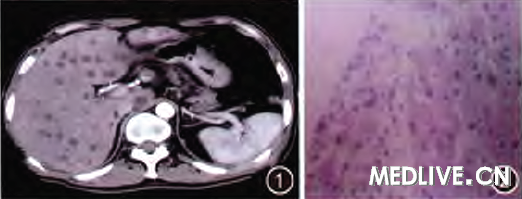

入院后给予抗感染(头孢地嗪)、护肝(还原型谷胱甘肽)、退热 (双氯芬酸钠栓)营养支持等处理;连续3 d患者精神较差,体温仍高,最高达40.5℃,高热时头痛明显、伴四肢乏力,应用退热栓后可控制数小时,曾解黑色大便1次,量不多尚成形;彩色B超示:肝脏体积增大,内可见多个大小不等低回声光团,提示肝内多发实质性占位(肝癌可能):增强CT示:肝内多发性占位,考虑为肝寄生虫病及肝脏肿瘤(图1)。

遂行胃、肠镜检查均无阳性发现。在B超定位下行经皮肝穿刺活检术,取出灰白红色相间实质性肝组织4条送检,病理检查提示炎性细胞浸润(图2),诊断为多发不典型肝脓肿、肝脏炎性假瘤(IPL)形成,并继续强化抗感染及相关支持治疗。

诊断考虑为肠道致病菌经血行播散所致败血症及多发不典型肝脓肿、IPL形成,而黑便为急性应激所致。肝脓肿大多为囊性占位,该患者行肝穿抽出实质性组织,可能与早期使用抗生素、致病菌毒力较低、肝脓肿尚未完全液化有关。随着医疗条件的提高、抗生素的早期广泛应用及疾病自身演变阶段的不同,肝脓肿影像学征象可呈现不典型、多样性改变。

IPL影像学特征为病灶周围环行强化环与不典型肝脓肿鉴别极为困难。本例影像学提示肝内多发性病变,多发病例少见且多被误诊为恶性肿瘤行手术切除后经病理检查证实。

因此,与各种肿瘤、囊肿,脓肿、包虫病、血管瘤等鉴别主要靠病理检查,其特征为纤维结缔组织增生伴以浆细胞为主的慢性炎性细胞浸润。肝脏良性占位性病变极易被误诊,对于影像学鉴别困难的患者在排除肝包虫病后应及早行肝穿病检明确诊断治疗上多主张手术切除,Sari等【Turk J Gastroenterol 2010 Sep;21(3):308-12】认为可行保守治疗并随访。